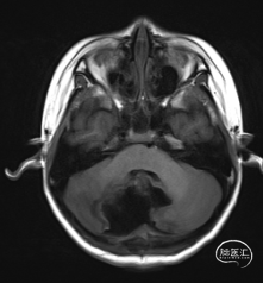

术后MRI